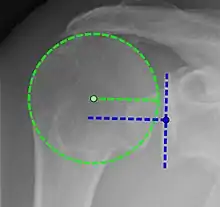

X-ray projectional radiography cannot directly reveal tears of the rotator cuff, a 'soft tissue', and consequently, normal X-rays cannot exclude a damaged cuff. However, indirect evidence of pathology may be seen in instances where one or more of the tendons have undergone degenerative calcification (calcific tendinitis). The humeral head may migrate upwards (high-riding humeral head) secondary to tears of the infraspinatus, or combined tears of the supraspinatus and infraspinatus.[47] The migration can be measured by the distance between:

- A line crossing the center of a line between the superior and inferior rims of the glenoid articular surface (blue in image).

- The center of a "best-fit" circle positioned over the humeral articular surface (green in image)

Normally, the former is positioned inferiorly to the latter, and a reversal is therefore indicating a rotator cuff tear.[47] Prolonged contact between a high-riding humeral head and the acromion above it, may lead to X-rays findings of wear on the humeral head and acromion and secondary degenerative arthritis of the glenohumeral joint (the ball and socket joint of the shoulder), called cuff arthropathy, may follow.[46] Incidental X-ray findings of bone spurs at the adjacent acromioclavicular joint may show a bone spur growing from the outer edge of the clavicle downwards towards the rotator cuff. Spurs may also be seen on the underside of the acromion, once thought to cause direct fraying of the rotator cuff from contact friction, a concept currently regarded as controversial.